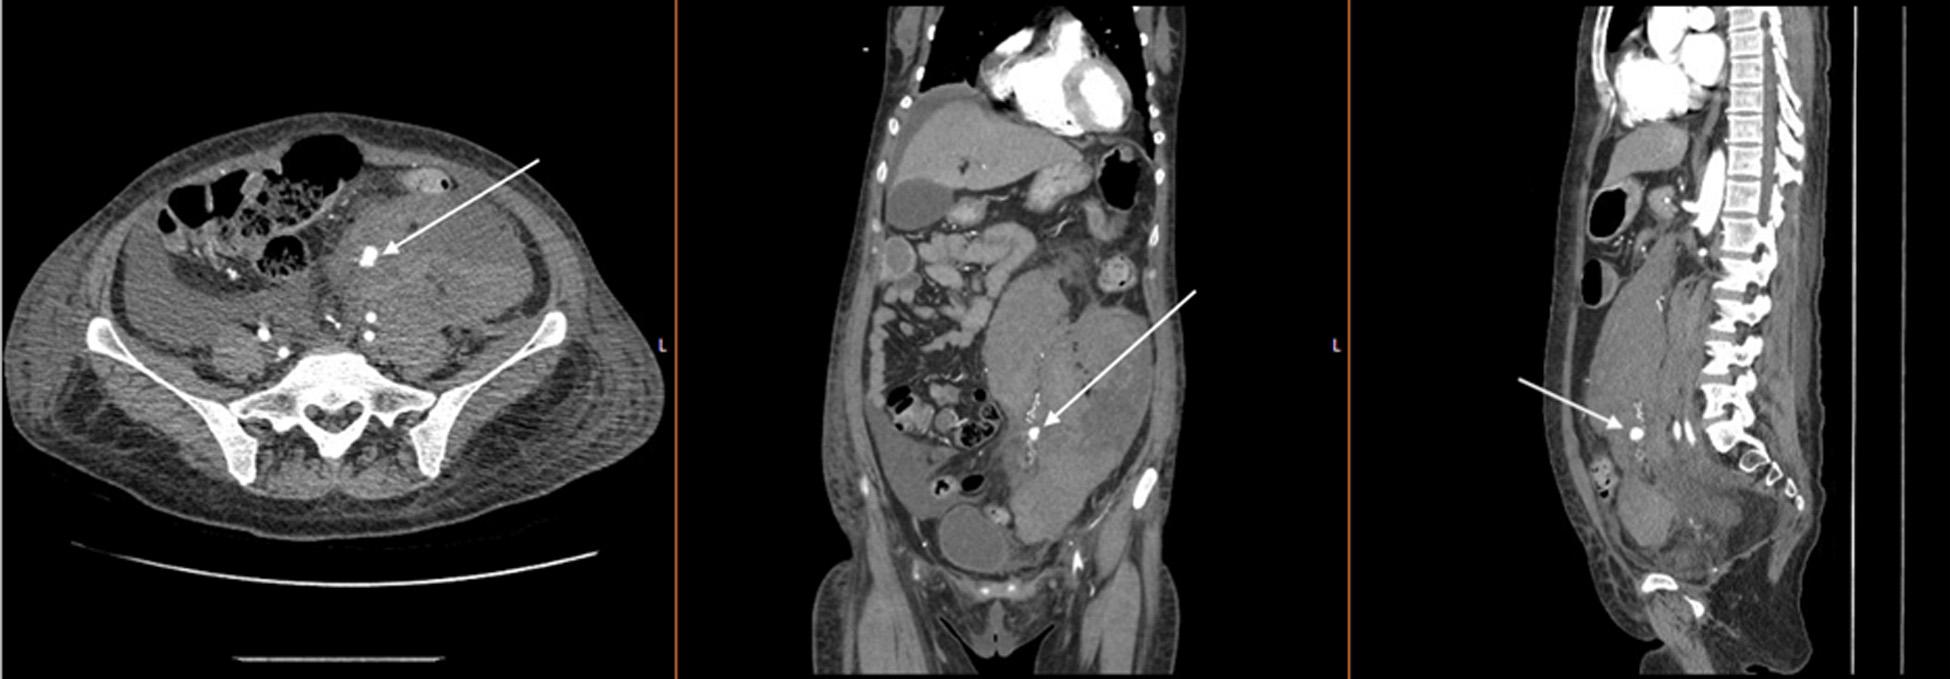

CaseReport: Wepresentacaseofa75-year-oldfemalewhopresentedwithnon-specificabdominal pain.Therarewhirlpoolsignoncomputedtomographyidentifiedamesentericvolvulusasthecauseof smallbowelobstruction.Shewastakentotheoperatingroomand,aftersuccessfulresectionofthesmall bowel,sherecoveredandultimatelywasdischargedhome.

Image. Computedtomographyabdomenwithintravenouscontrast demonstratingdilated, fluid-filledloopsofsmallbowelandapattern ofswirlingmesentericvesselscalledthewhirlpoolsign(arrow).

Onpresentationthepatientwasinnoacutedistressbut wasclammyandtachycardicatarateof118beatsper minute.Onexam,herabdomenwasdiffuselytenderwithout distentionorperitonealsigns.Shehadanelevatedwhite bloodcellcountat17 × 103 permicroliter(K/μL)(reference range4.5–11.0K/μL),anINRof5.5,andalacticacidof 3.7millimolesperliter(mmol/L)(0.4–2.0mmol/L).An abdomenandpelvisCTwithintravenous(IV)contrast showed findingssuspiciousforclosedloop,smallbowel obstruction.TheCTalsodemonstratedevidenceofswirling ofthemesentericroot,knownasawhirlpoolsign(Image, Video).The findingsofthewhirlpoolsignonCTsuggested mesentericvolvulusasthecauseofherbowelobstructionand promptedemergentsurgicalconsultation.

pathology.However,radiographsareofteninconclusivein midgutvolvulusbecauseevenapositive “doublebubble” signindicatingasmallbowelobstructiondoesnotruleouta concomitantmidgutvolvulus.7 Computedtomographywith IVcontrastgivesmuchgreaterdetailoftheabdomenandcan provideevidencesuggestiveofamidgutvolvulus.ClassicCT imaging findingsincludeawhirlpoolsignoftwisted mesentery,malrotatedbowelconfiguration,inverted superiormesentericarteryandsuperiormesentericvein relationship,bowelobstruction,andfree fluid/freegasin advancedcases.8 ThewhirlpoolsignseenonCTrepresents themesenteryandsuperiormesentericveinwrapping aroundthesuperiormesentericarteryina counterclockwisedirection.